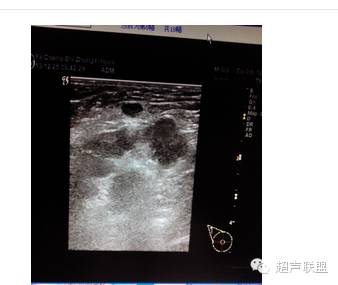

患女47岁,一周前洗澡时发现右略内陷,来诊。外科扪诊:于右乳腺乳晕正下方处扪及一硬结,质略硬,活动良好,轻微压痛。病史:患者无结核病及肝炎史,无家族肿瘤病史;曾有过多次乳肪胀痛,未去医院就诊,口服“乳癖消”等治疗乳腺增生的药物,好转后停用,量不详。现血常规化验未见异常。

声像图表现:于右乳腺相当于六点钟,距约1.5cm处见一大小约1.0x0.6cm低回声肿物,边界尚清,形态不规,周边可检出动脉频谱样血流信号,RI为0.67,余腺体回声粗糙,未见占位性病变。右腋下另见数个淋巴结,较大的为1.4x0.8cm,边界清,周边呈低回声,中心部呈高回声。

超声印诊:1.右乳腺低回声肿物,性质待定

2.右腋下淋巴结肿大

病理结果:浆细胞性乳腺炎